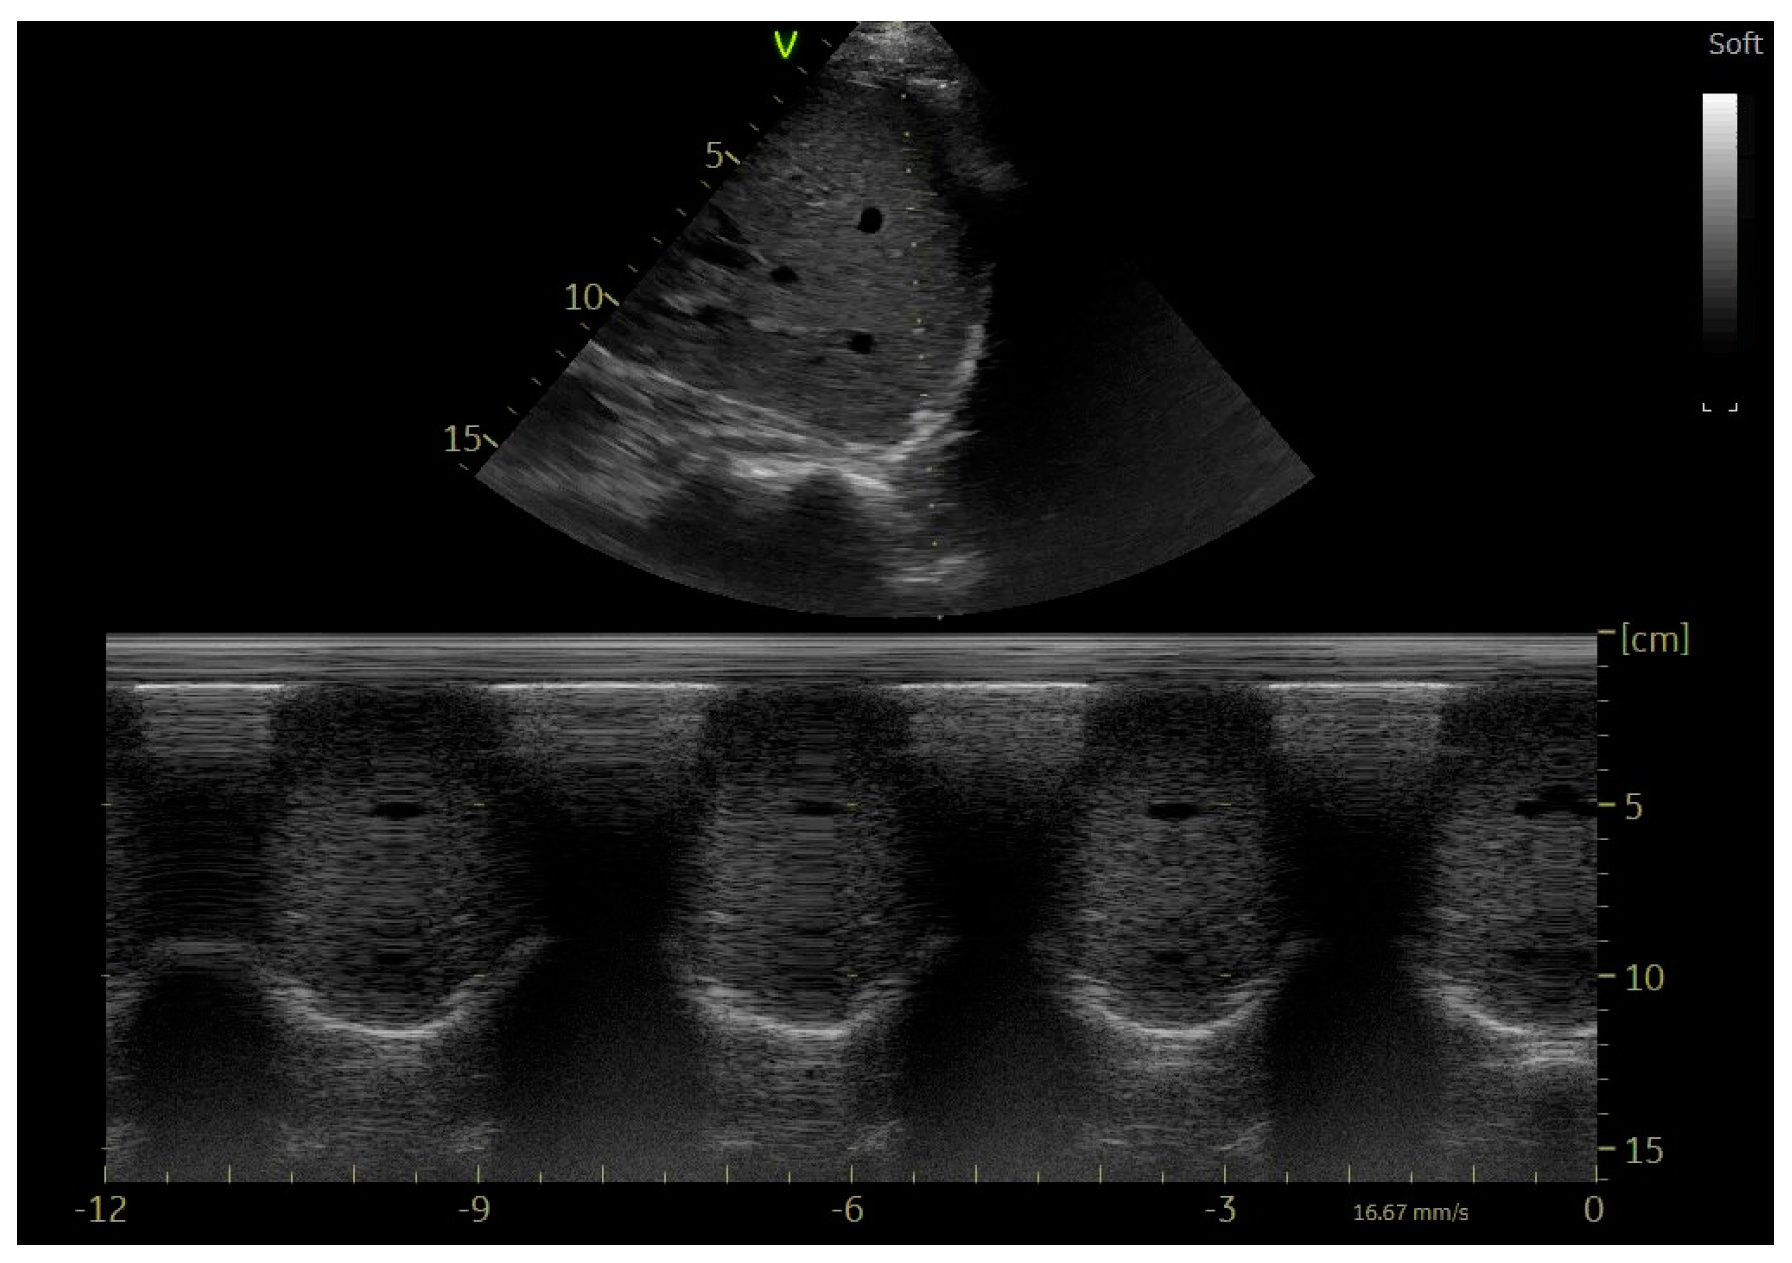

9. Echocardiographic Assessment of Diaphragmatic Function

10. Evaluation of the Diaphragm in Ventilated Patient